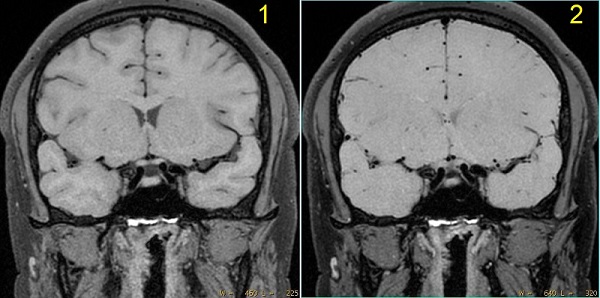

Figure 4. Cube and MSDE with and without fat saturation

Table 5. Image legend

NumberDescription

1Cube and MSDE without fat saturation. Note the ringing artifact from surface fat.

2Cube and MSDE with fat saturation. Ringing artifact is eliminated.